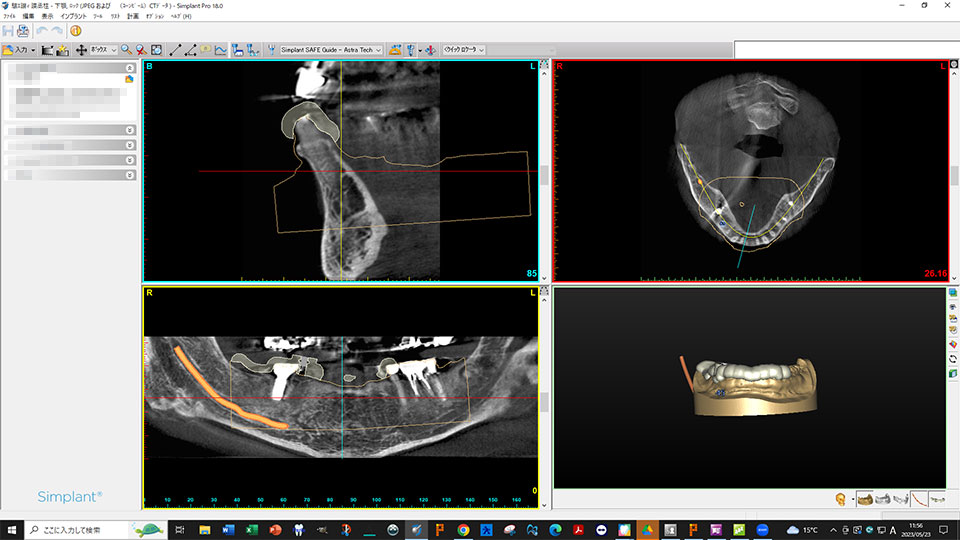

当院のインプラントの特徴

ガイデッドサージェリー

当院では、ガイデッドサージェリーを導入しております。ガイデッドサージェリーは、通常のインプラント手術とは異なり、身体への負担を軽減した治療方法です。この方法では、CT撮影によって得たデータを利用して、治療のためのガイドを作成します。ガイドを使用することで、シミュレーション通りに手術を進め、3D画像で骨や神経の位置を確認しながら、理想的な位置にインプラントを埋入することができます。さらに、周囲を傷つける心配をせずに手術に集中することができます。

ガイデッドサージェリーのメリット

①理想的な位置にインプラントを埋入できる

顎の骨や患者様の個別の要素に基づいて詳細なデータを収集し、事前に分析を行います。これにより、術後の違和感を最小限に抑えることができます。また、高度な精密治療にも対応できるため、精度の高いインプラント手術が可能です。

②手術中の患者様の負担が軽減する

事前に埋入位置が確定しているため、歯肉を大きく切開する必要がありません。出血や痛み、腫れが少なく、外科治療に抵抗のある患者様の負担を軽減できます。

③インプラント手術のリスクを回避できる

通常の手術では、インプラントの埋入位置が適切でない場合、大量出血や神経への損傷などのトラブルが起こる可能性があります。 事前に血管や神経の位置を把握し、埋入位置を確定するため、これらのリスクを回避することができます。

④手術時間を短縮できる

埋入位置の正確な計画により迷いがなく、大きな歯肉切開が不要なため効率的です。 インプラントサイズも事前に決定されるため、スムーズな手術が可能。